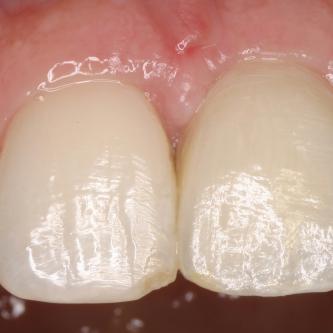

Exemple 3: Un implant à la place d'une incisive latérale supérieure droite. Sur cette image on voit le moignon en titane qui est vissé sur l'implant.

Exemple 3: Puis sur ce moignon, la couronne en céramique est scellée.

Exemple3: La couronne en place.